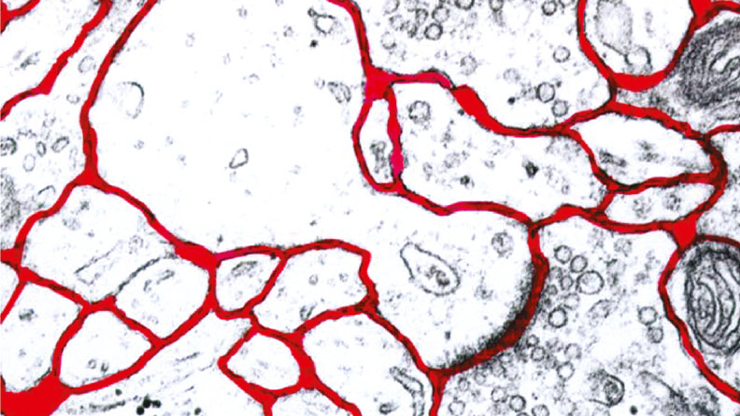

Vivi Rottschäfer presents a mathematical model that studies the processes governing the concentration profile of drugs in the brain.